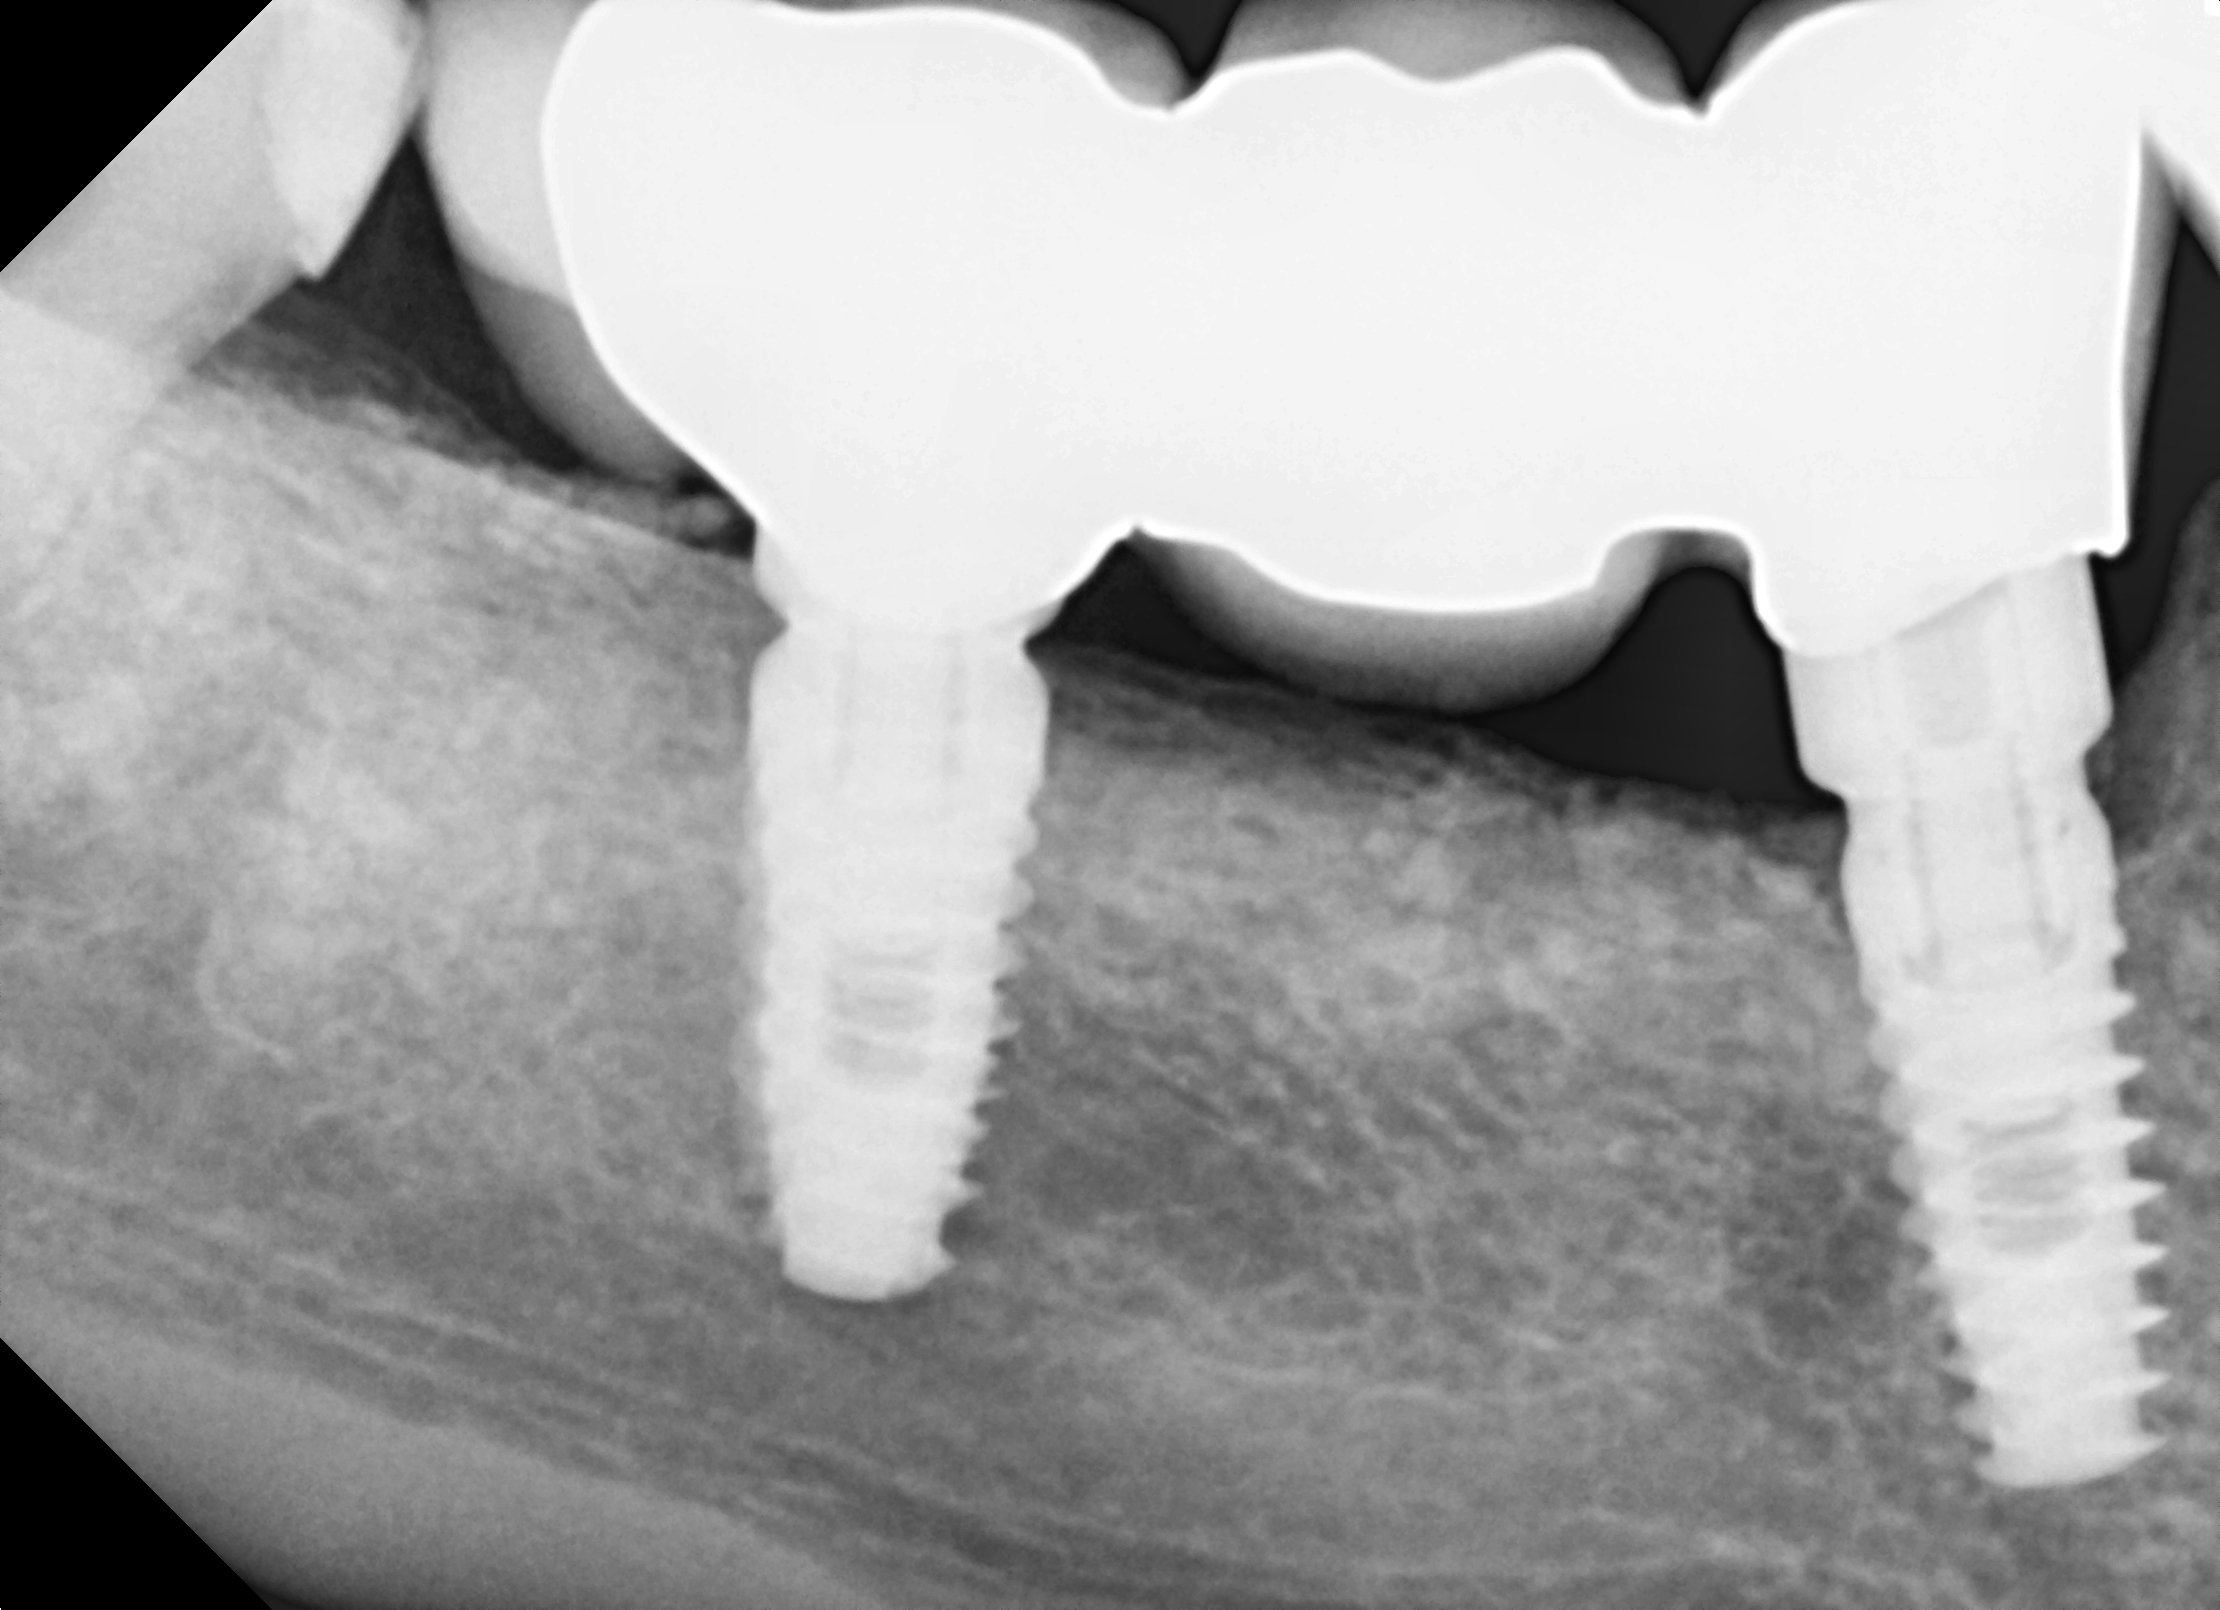

Następnie wykonano suprastrukturę protetyczną (most pełnoceramiczny) cementowaną (ryc. 24).

Ryc. 24. Łączniki protetyczne

Kontrola po 12 miesiącach wykazała prawidłową strukturę kości i tkanek miękkich (ryc. 25, 26).

Ryc. 25. Kontrla rtg 12 miesięcy po obciążeniu funkcjonalnym.